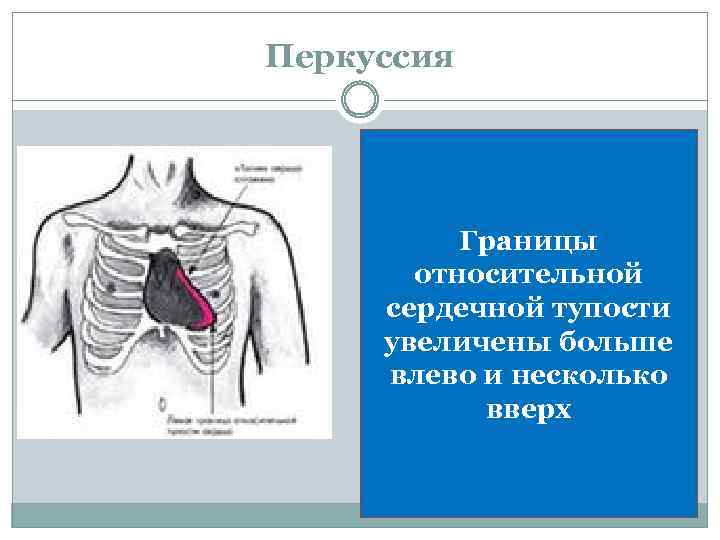

Перкуссия Границы относительной сердечной тупости увеличены больше влево и несколько вверх